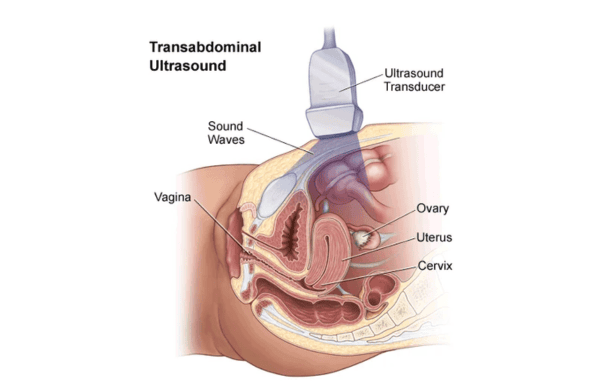

2D Ultrasonography

A basic ultrasound that produces flat, black-and-white images of organs or fetus.

TVS (Transvaginal Sonography)

An ultrasound where a probe is inserted into the vagina to get clear images of pelvic organs.

What is the difference between TVS and abdominal ultrasound?

TVS (Transvaginal Sonography) provides more detailed and clearer images of the uterus and ovaries compared to abdominal ultrasound, especially in early diagnosis.